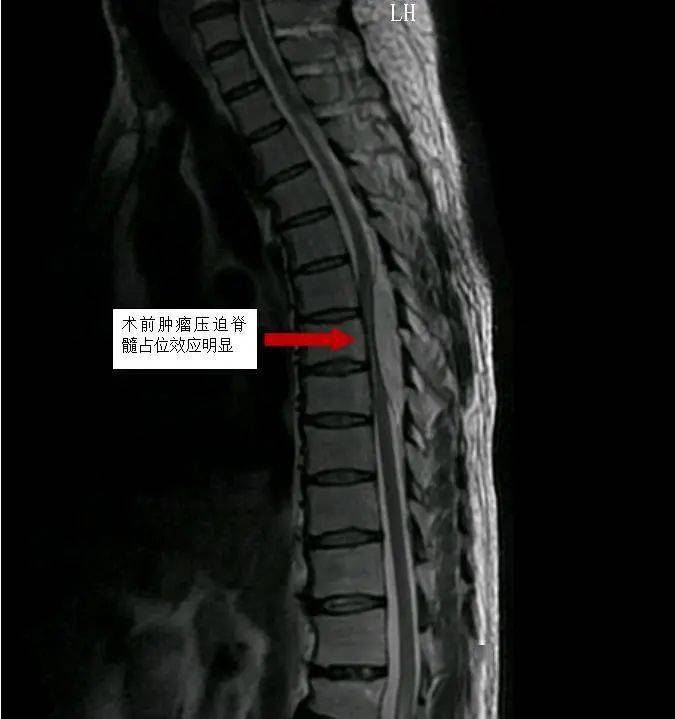

入院后,胸椎增强磁共振示胸6-8椎体层面椎管后缘梭形异常信号-考虑髓

图片尺寸675x719